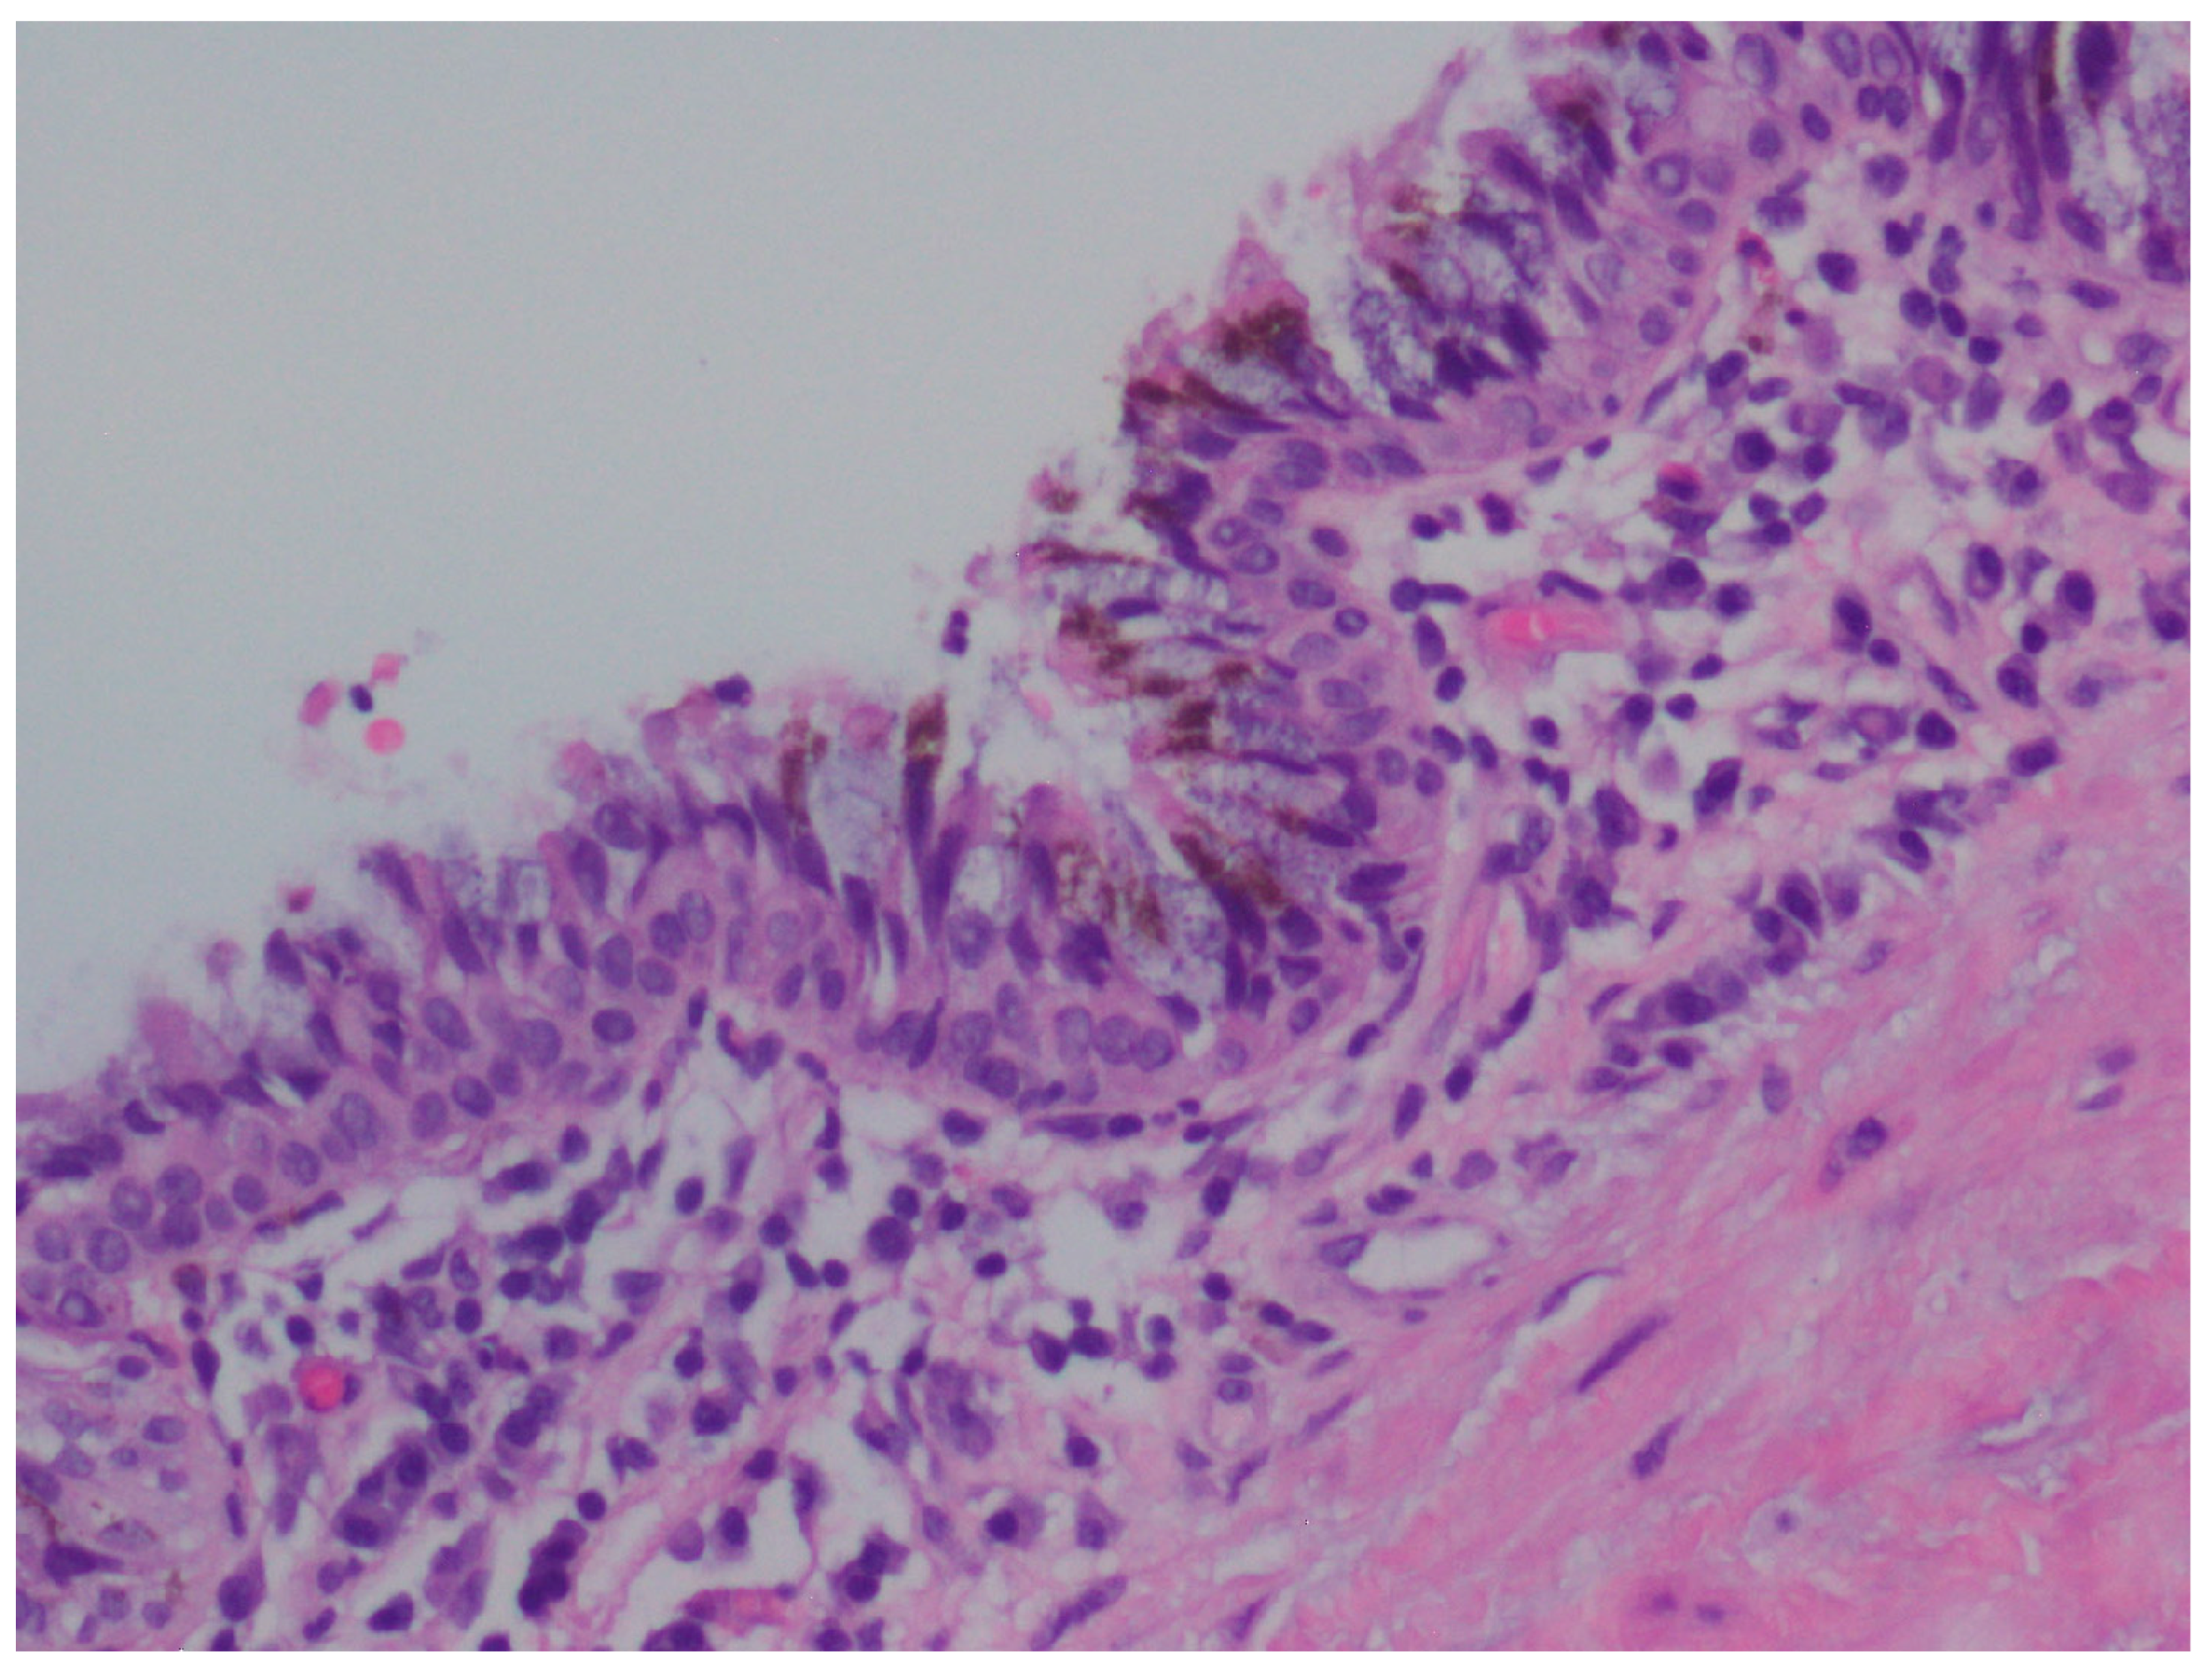

A Rare Case of a Large Composite Endometrioma–Mature Cystic Teratoma: The Importance of Surgical Treatment and Pathologic Diagnosis

2. Case Presentation